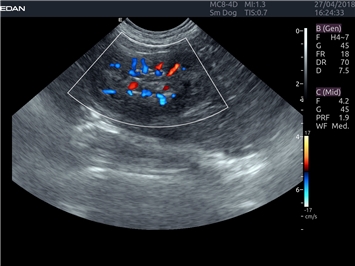

EDAN Acclarix LX4 VET

EDAN Acclarix LX4 VET представляет собой профессиональную ультразвуковую систему, специально разработанную для ветеринарных исследований. Сочетание стабильности, высокой производительности и эффективности делает эту систему идеальным выбором для современной ветеринарной практики.

Режимы акустической прозрачности 3D:

Да

Трехмерная реконструкция ЦДК:

Энергетический допплер:

Цветовой допплер: